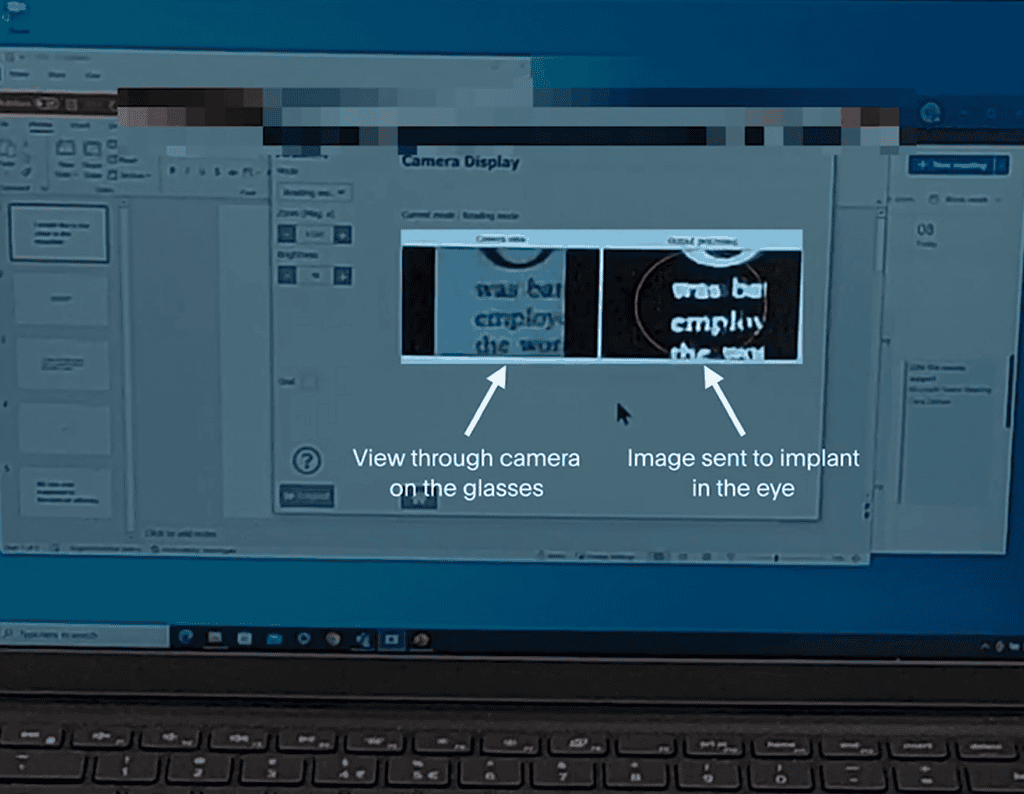

ชิป Prima ประกอบด้วยชิปสี่เหลี่ยมจัตุรัสขนาด 2 มม. ที่ถูกผ่าตัดวางไว้ใต้จอประสาทตา ตรงส่วนหลังสุดของลูกตา โดยใช้เวลาผ่าตัดนานถึง 80 นาที โดยจะใช้งานร่วมกับแว่นตาพร้อมกับกล้องที่จะบันทึกภาพ และส่งแสงอินฟราเรดไปยังชิป แล้วชิปดังกล่าวจะทำหน้าที่เสมือนแผงโซลาร์เซลล์ขนาดเล็ก ที่จะแปลงแสงเป็นการกระตุ้นไฟฟ้า และส่งไปยังสมอง จากนั้นสมองจะตีความสัญญาณดังกล่าวเป็นภาพ ซึ่งเป็นการเลียนแบบกระบวนการการมองเห็นตามธรรมชาติ

Prima แตกต่างจากอุปกรณ์ปลูกถ่ายจอประสาทตาอื่นๆ ตรงที่มันช่วยให้มองเห็นรูปร่าง ลวดลาย และองค์ประกอบภาพอื่นๆ ของวัตถุได้ อย่างไรก็ตาม สิ่งที่ผู้ใช้มองเห็นนั้นไม่ใช่การมองเห็นแบบ “ปกติ” :ซึ่งประการหนึ่งก็คือ ผู้ใช้จะมองไม่เห็นเป็นสี แต่จะมองเห็นเป็นภาพที่ผ่านการประมวลผลแล้วซึ่งจะเป็นสีโทนเหลือง